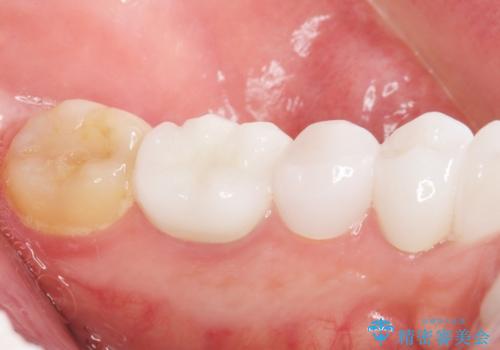

クラウンの色味・形態の修正や患者様のお仕事のご都合で来院できない期間があったことにより、予想より治療期間が長くなってしまいましたが、審美的な仕上がりにご満足頂けました。

矯正治療で歯並びを整えたいというのが歯科医師である私の本心でしたが、患者様の強いご希望によりオールセラミッククラウンによる補綴治療を行いました。

クラウンの色味に関して、自然な白さ(シェードA1~NW0.5)のクラウンを作製・試適したところ「もっと白くしたい」と希望され、当院で最も明度の高い色(シェードNW0)に修正しました。

被せ物の種類:オールセラミッククラウン スタンダード (シェード:NW0)